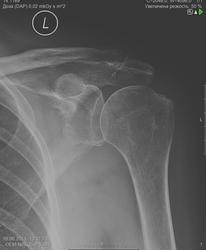

На Rg-грамме левого плечевого сустава определяется незначительный субхондральный склероз суставной поверхности. Краевые костные разрастания по нижнему краю суставной поверхности. В области акромиально-ключичного сустава определяется кистовидная перестройка костной ткани, костная перемычка по нижней поверхности сустава.

Заключение: артроз левого плечевого и акромиально-ключичного суставов. Оссификация акромиально-ключичной связки?

Нет костной перемычки. С кистовидной перестройкой тоже как- то не очень.

Считаю, что артроза плечевого сустава нет. На акромиальный конец ключице не нравится. Хотелось бы для сравнения другой сустав, если есть возможность.

"Краевые костные разрастания по нижнему краю суставной поверхности." Не указано стрелкой. Коллега! Главный признак артроза - не есть изменения окружающих тканей! Тем более в надцать лет. Почитайте про артрозы, а то право - неловко всем...

Разрастаний по нижнему полюсу суставной поверхности лопатки нет, она такой формы сама,.. как слеза или как лимбус у поясничного позвонка.) Оссификация ключично-акромиальной связки была бы видна, если бы снимок в режиме выполнен был, а пока... почти догадкой осталась, ага.)